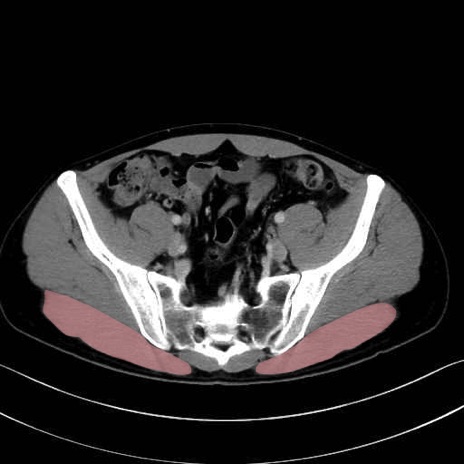

大殿筋 (Gluteus maximus)